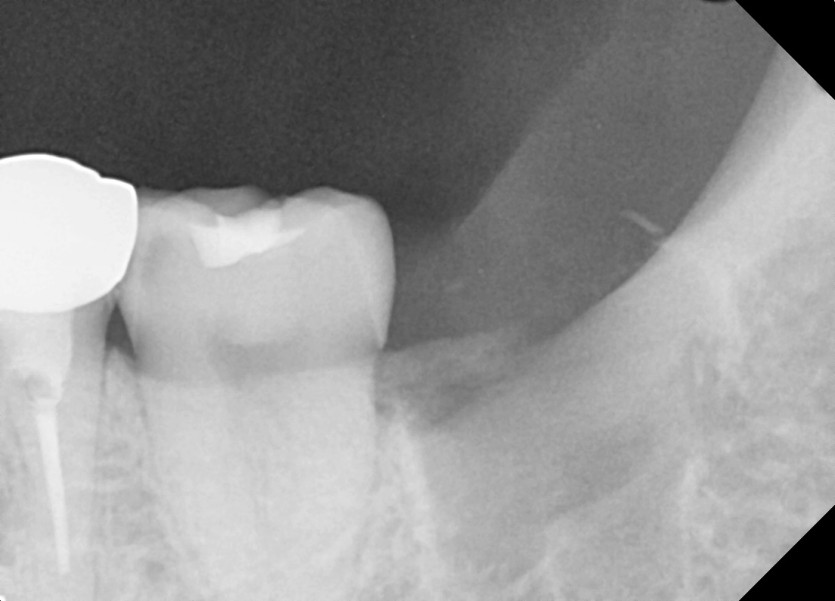

#38 사랑니 발치

구강외과 전문의가 당일 발치했습니다.